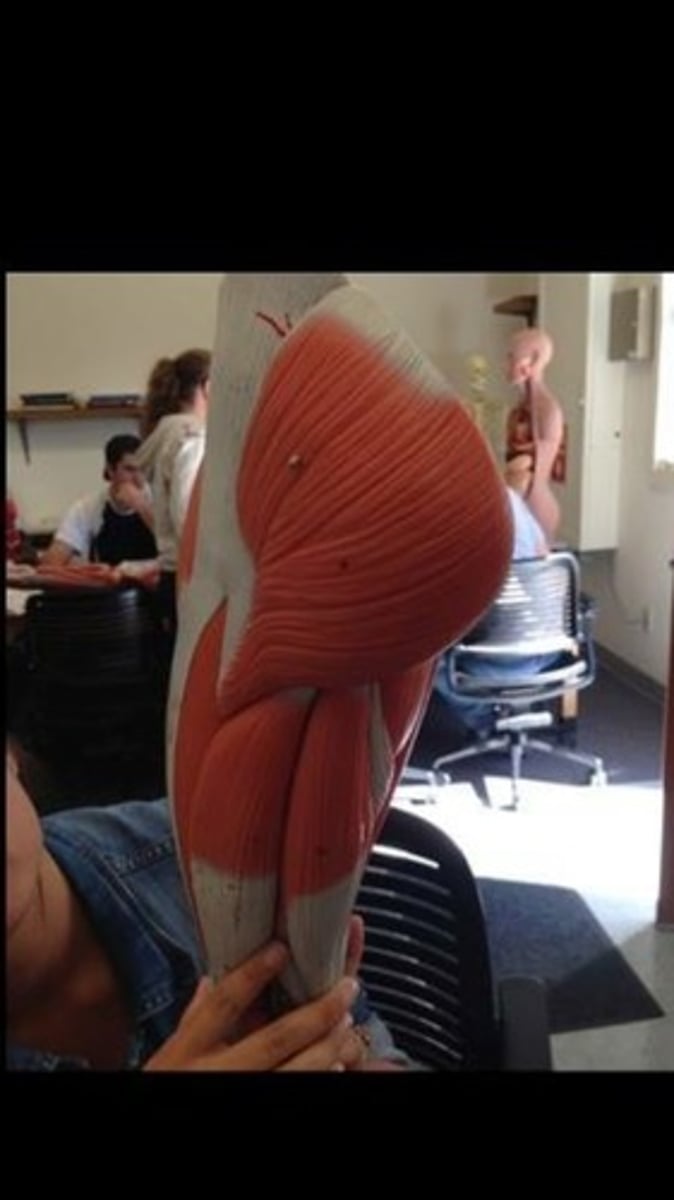

Skeletal muscle terms and structure

114 Terms